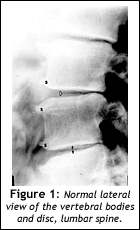

Instead of describing the findings on the patient's films and pointing out the problems, I decided to let the patient tell me what was wrong by first showing her what a normal spine looked like; and how the vertebral bodies and facets performed as a motor unit to provide the support and mobility that allows us perform the activities of daily living that we just assume we take for granted.

First I showed her a print of a normal lumbar spine:

I explain the motor unit in very simple terms. For example, I explain that there is a disc with two left and right joints that make up the motor unit. The vertebral body and disc are the front half of the motor unit and the two vertebral joints are the back half. These two parts are its main structures. (You can fill in the gaps if you'd like, but don't get too complicated!)

I show her the two facets, one right, one left, on the back of the motor unit, and the disc vertebral body on the front of the motor unit. Next, I show her a normal disc and explain that the disc is something like a sponge or, even better, a tire that absorbs and cushions the vertebral bodies and joints so they don't jam together and grate bone on bone. I explain that the fluid in the disc acts like a sponge that absorbs stress.